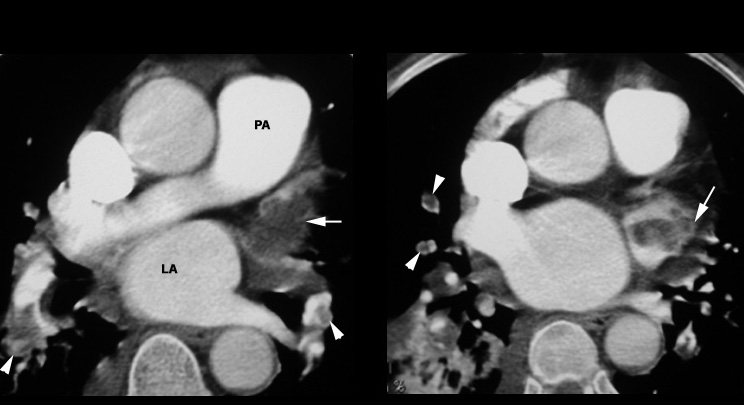

Pulmonary Embolism / Left Atrial Appendage clot

Arrowheads pointing to pulmonary artery branches with intraluminal clots. Arrow: Left atrial appendage with thrombus.